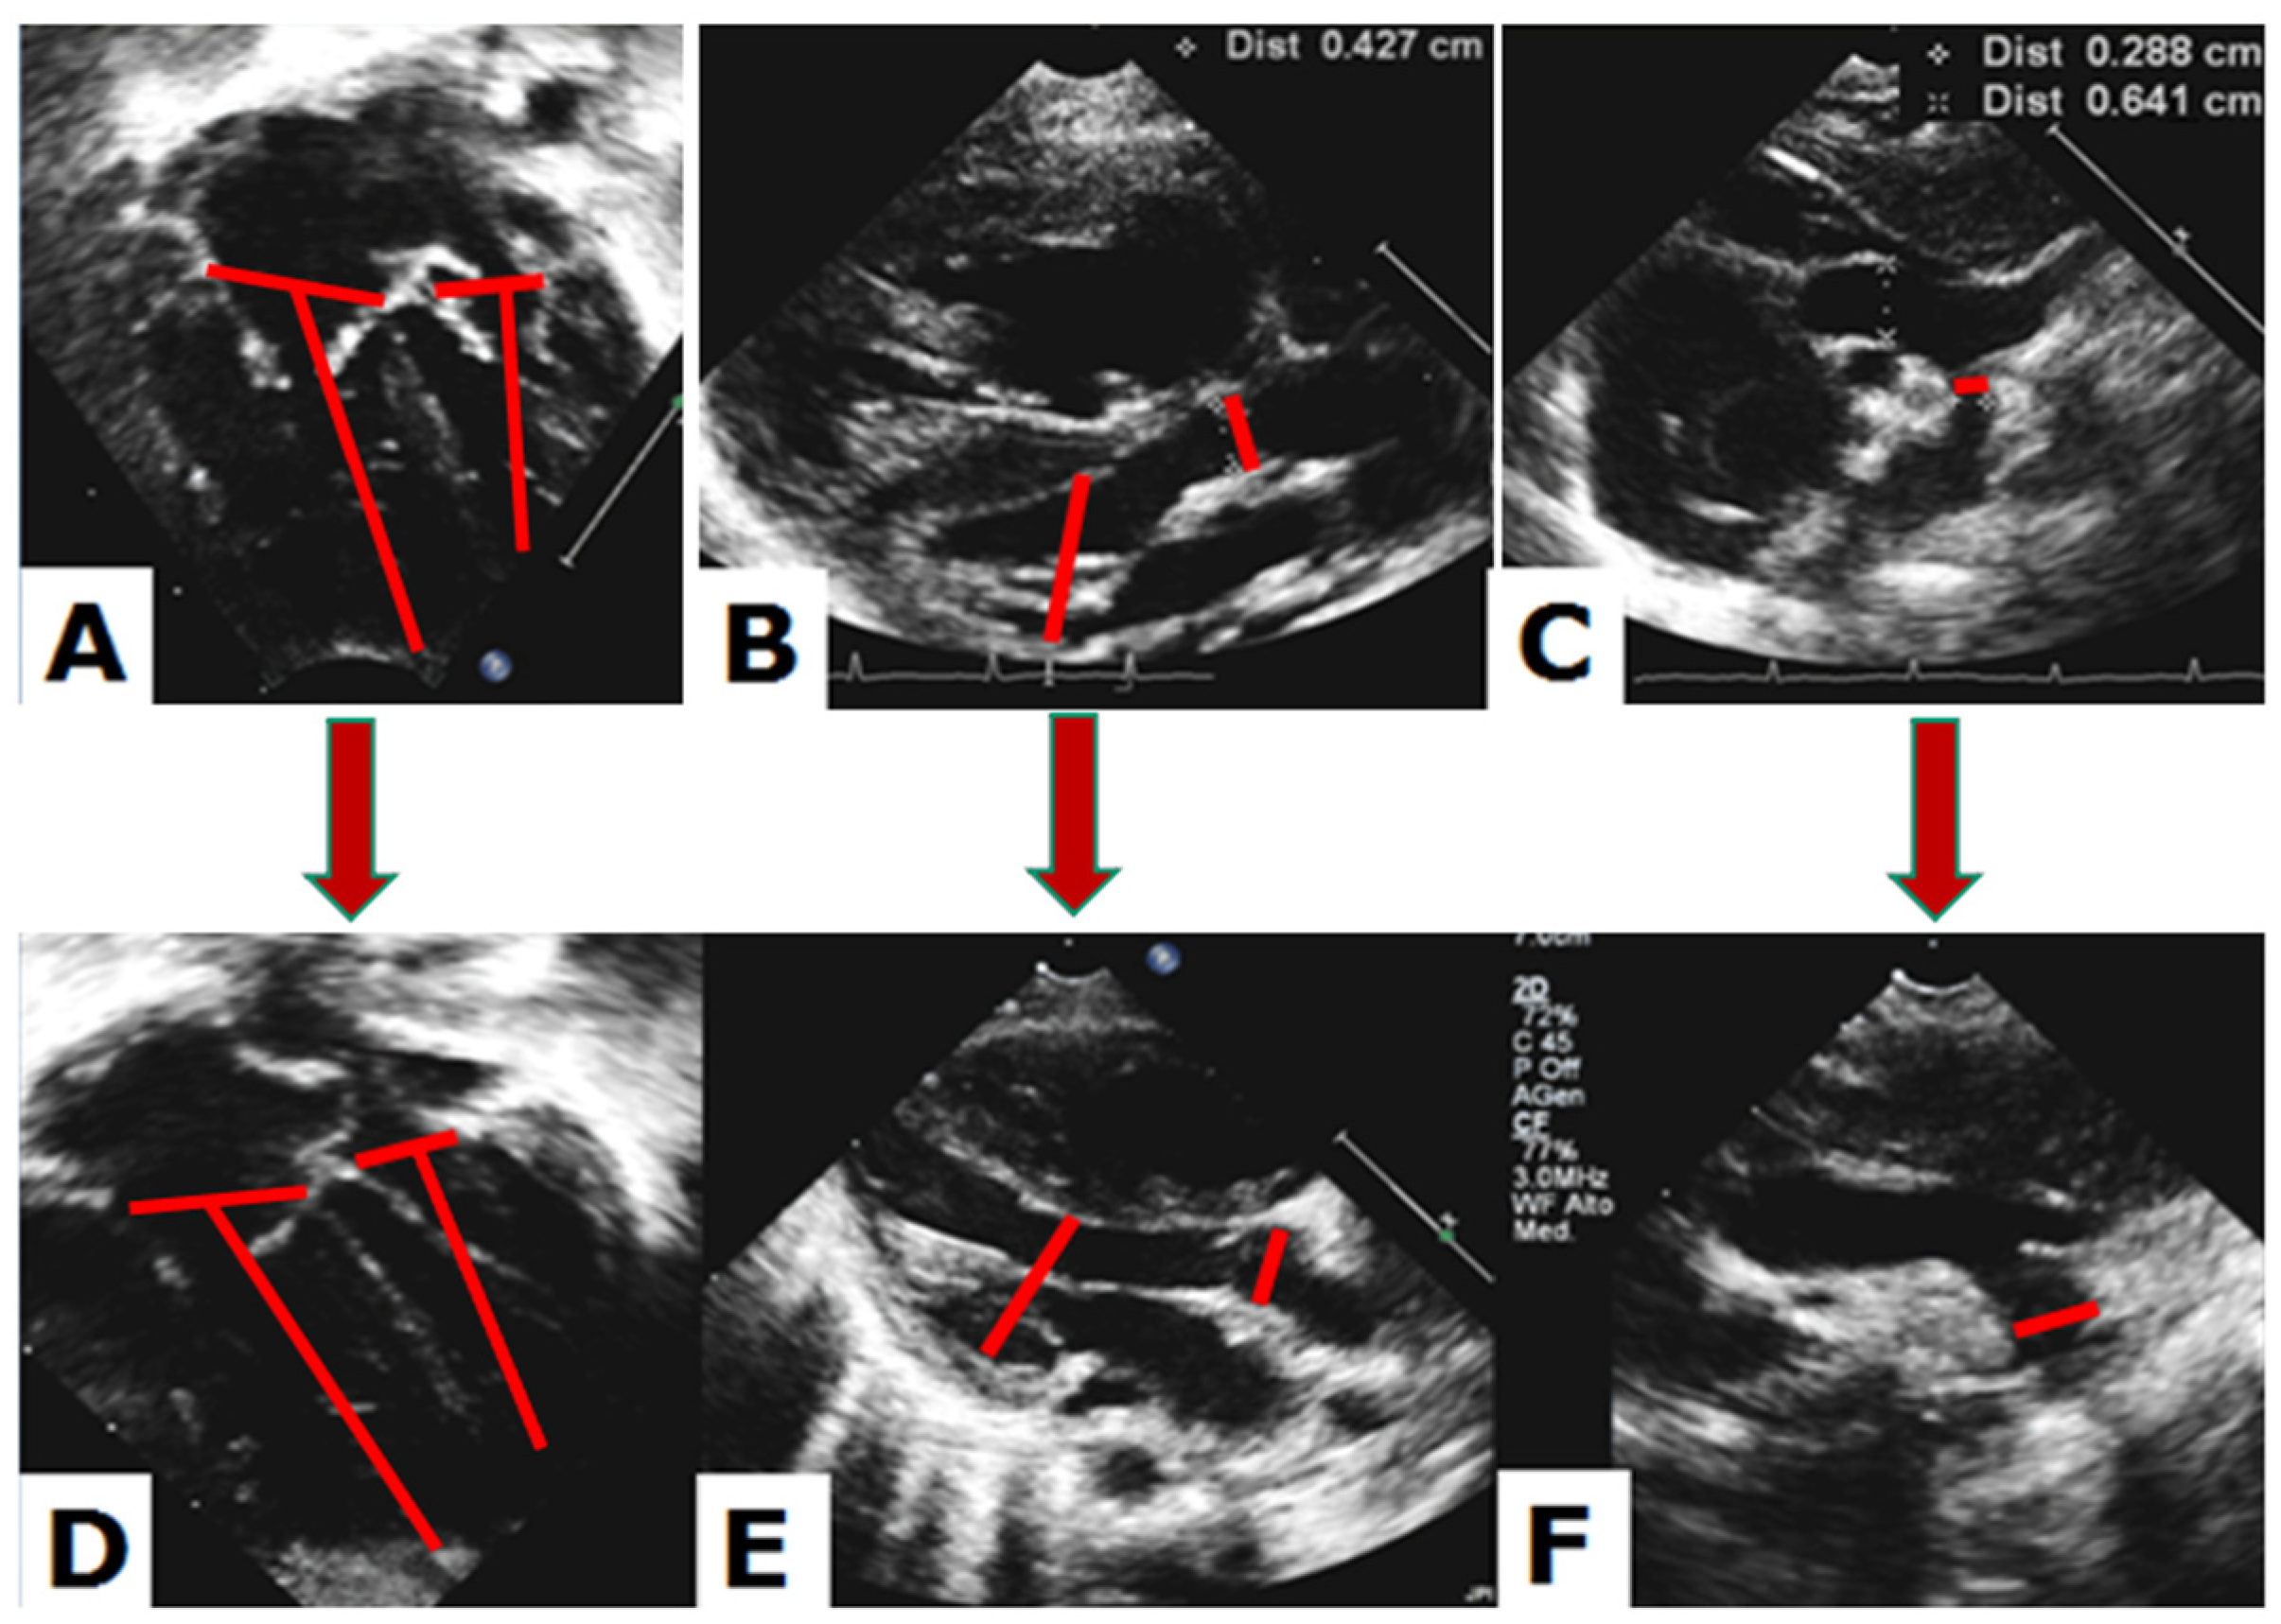

3.2. Qualitative Echocardiographic Evaluation